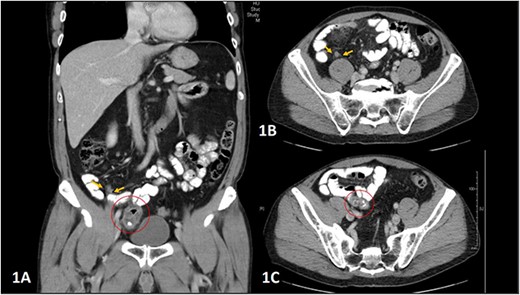

A 62-year-old man presented to the emergency department with a 1-day history of worsening right lower abdominal pain associated with nausea and fever. His medical history includes a transurethral resection of the prostate for acinar adenocarcinoma. Clinical examination revealed a soft abdomen with tenderness to palpation at the right lower quadrant. Inflammatory markers showed an elevated white cell count of 12 000/μL and a C-reactive protein of 23 mg/L. Computed tomography (CT) scan demonstrated both an inflamed small bowel diverticulum in the right lower quadrant and mild inflammation of the appendix (Fig. 1). The patient underwent laparoscopy the following day, which revealed a 3 cm inflamed MD adherent to the right anterior abdominal wall with localized peritonitis and a concomitant inflamed appendix (Fig. 2). Laparoscopic appendicectomy and limited small bowel resection with a side-to-side stapled anastomosis were performed simultaneously. Histopathology revealed Meckel’s diverticulitis with ulceration and abscess formation and mild appendicitis. He had an unremarkable recovery in the hospital and remained well on outpatient follow-up 4 weeks later.

(A–C) Abdominal CT scan showing coronal and axial planes (A and B), indicating the inflamed appendix, highlighted by yellow arrows, and coronal and axial planes (A and C) showing the diverticulum arising from a loop of small bowel extending to the right iliac fossa and right pelvis, highlighted within a red circle.